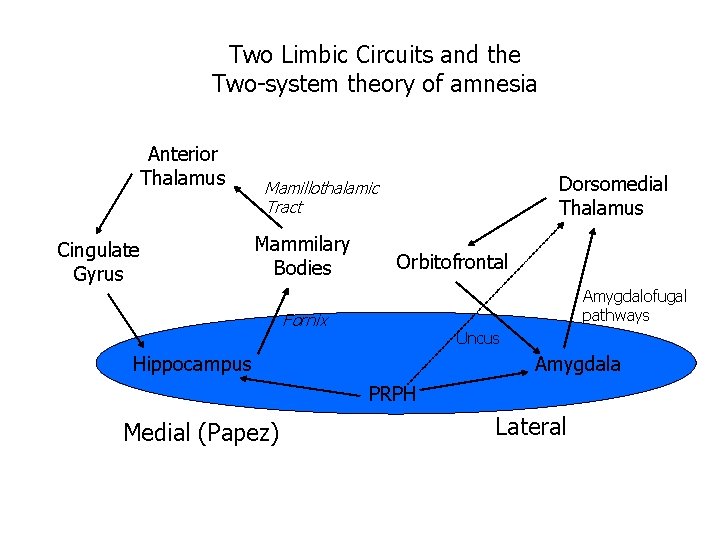

Two Limbic Circuits and the Two-system theory of amnesia Anterior Thalamus Cingulate Gyrus Dorsomedial Thalamus Mamillothalamic Tract Mammilary Bodies Orbitofrontal Amygdalofugal pathways Fornix Uncus Hippocampus Amygdala PRPH Medial (Papez) Lateral